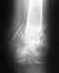

Здравствуйте! Подскажите, пожалуйста, у меня перелом бедра правой ноги в двух местах,

мне после операции наложили гипс от груди (корсетом) и на всю ногу до ступни. Можно ли мне немного срезать верх гипсового корсета со стороны живота, для того чтобы была возможность немного сгибать спину, для того чтобы присаживаться, а то я не могу даже сесть, извините, на унитаз.